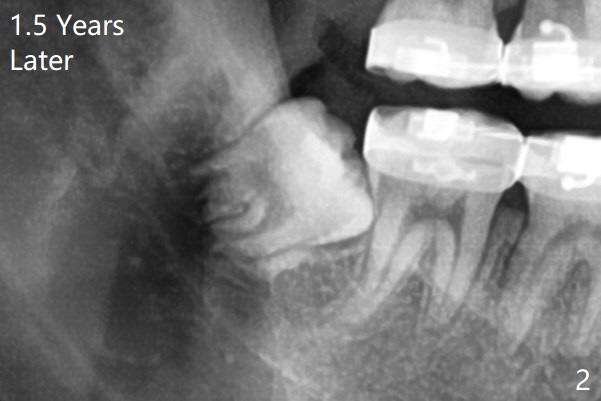

1.5年智齿牙根长长(图二)。1.5月后下颌智齿拔除放置Osteogen Plug(图三)。